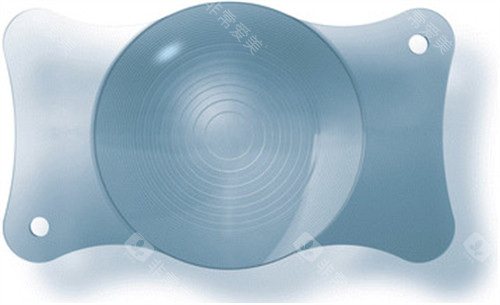

2. 环形襻设计,提升植入稳定性

其专有环形襻结构(如Aspira-aXA型号)通过360度环绕支撑囊袋,植入后稳定性较传统晶体提升显著。

这一设计在高度近视患者中表现尤为突出——眼轴较长导致囊袋张力不足,传统晶体易移位,而环形襻可模拟张力环作用,减少术后晶体偏心的概率。

3. Aspira-aXA:环形襻稳定型代表

技术亮点:360度环形襻设计,植入后晶体偏心风险降低,尤其适合囊袋张力不足的患者。

适用人群:较高度近视(眼轴>28毫米)或白内障术后需长期稳定视力的老年患者。

价格区间:单眼价格约9000-12000元,兼顾性能与成本。